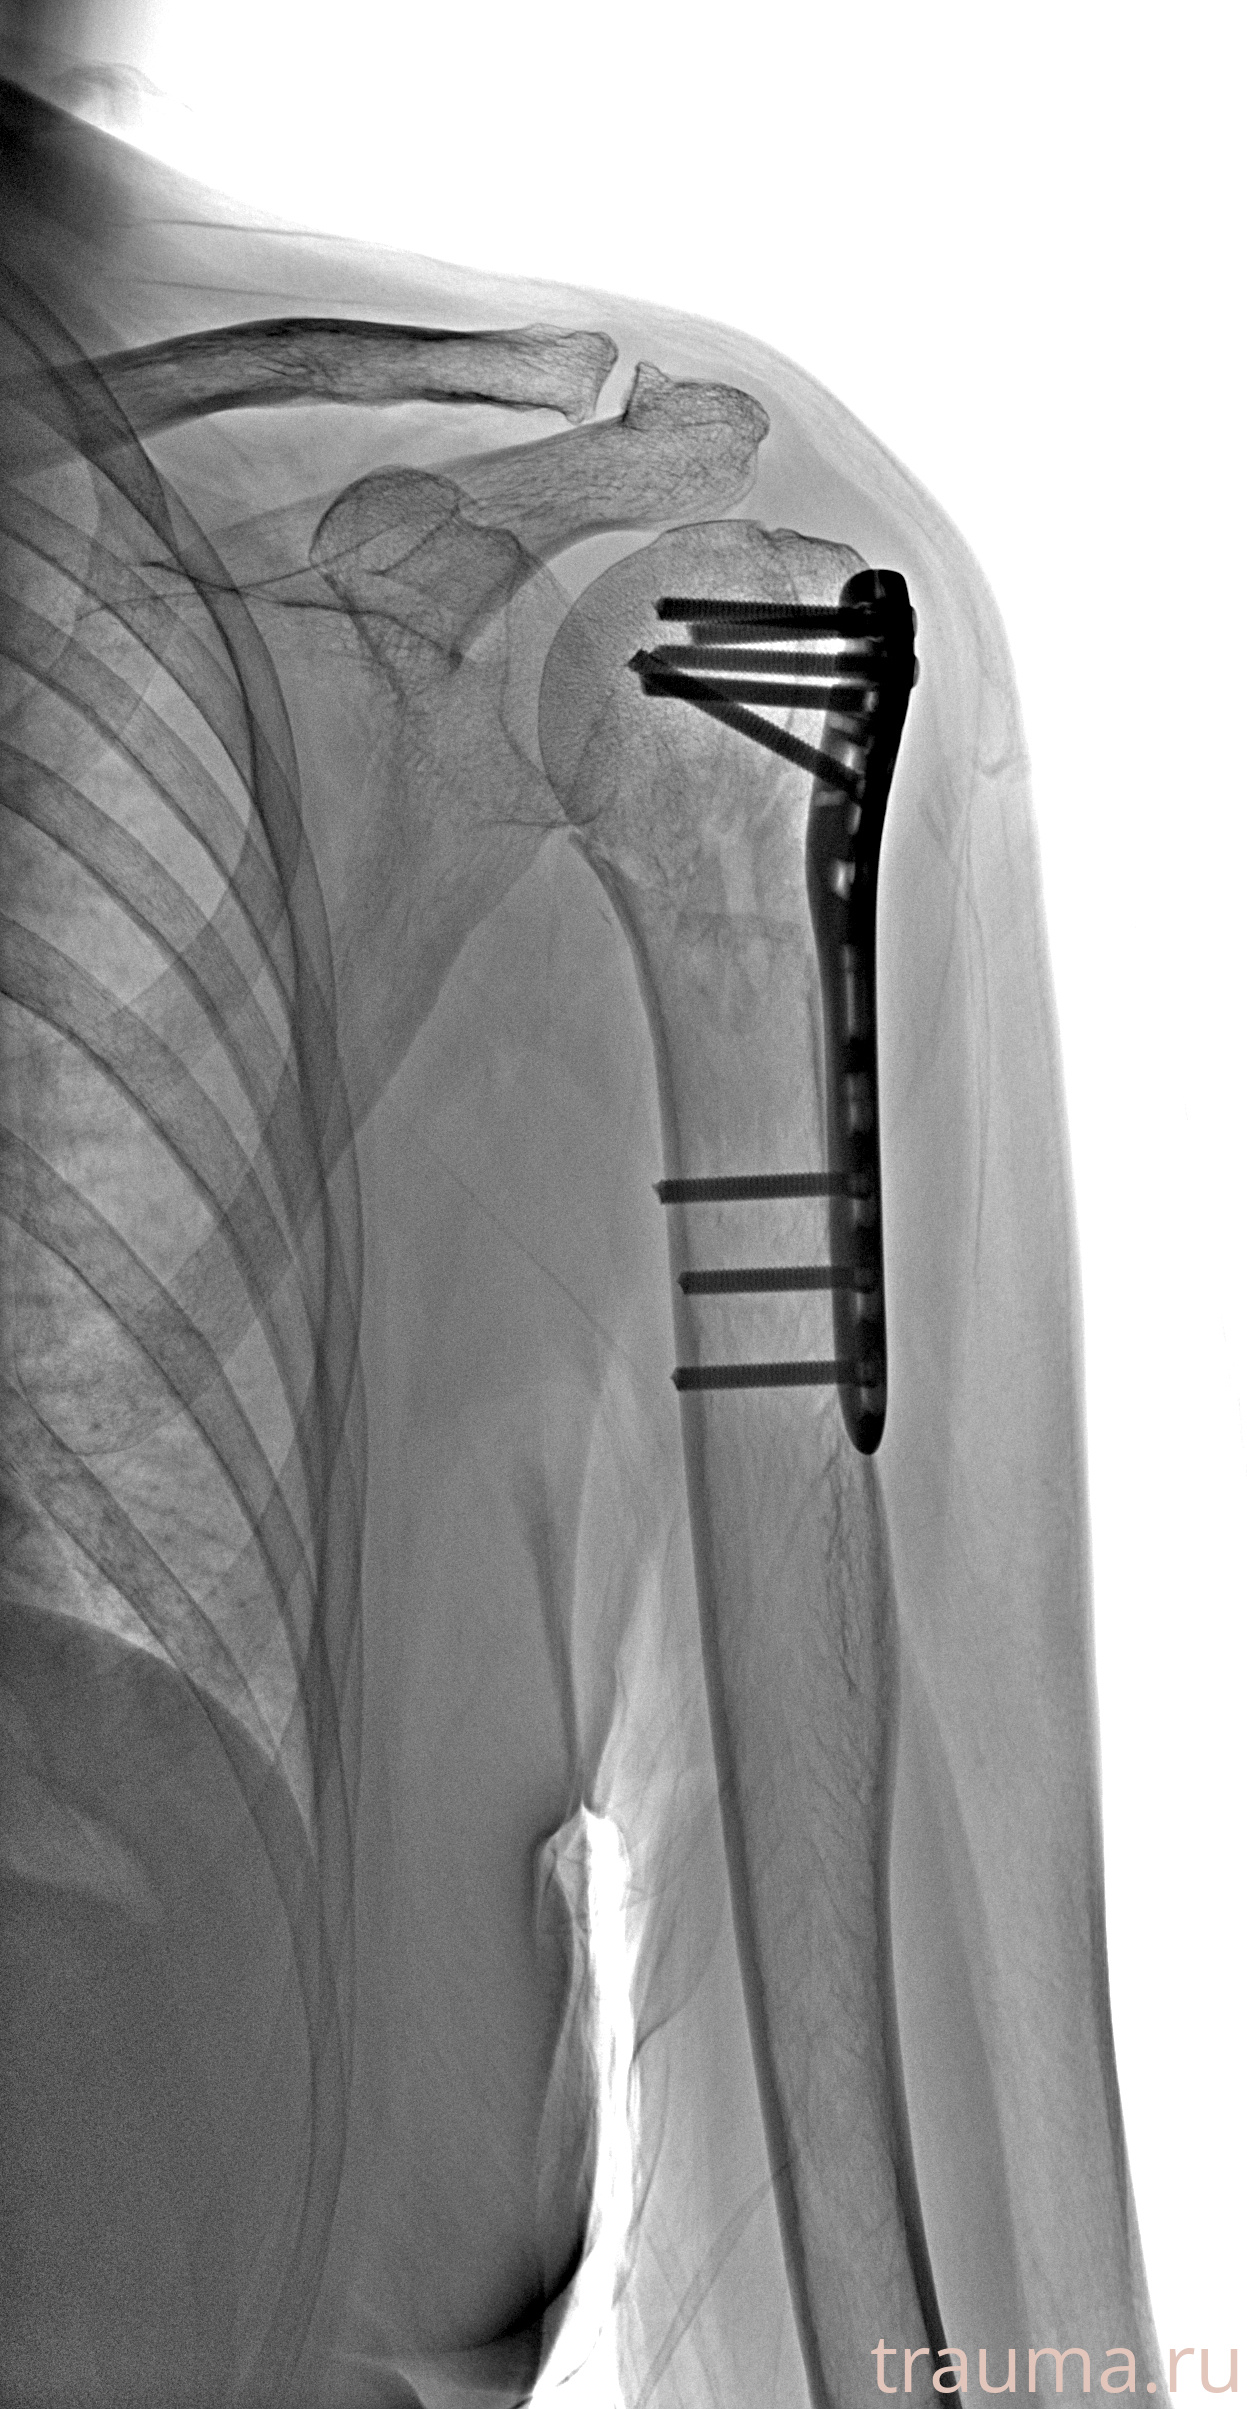

Рентгенограммы